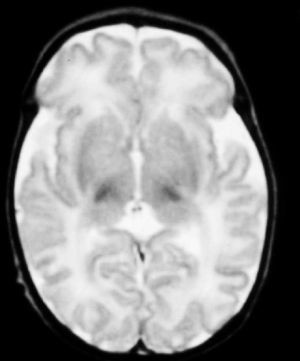

Fig. 1.Resonancia magnética.Secuencia T1 en plano axial. Hiperintensidad de señal que de forma simétrica afecta a núcleos palidales y subtalámicos.

A las 48 horas de su ingreso presenta una crisis de hipertonía, motivo por el que se realiza una resonancia magnética.